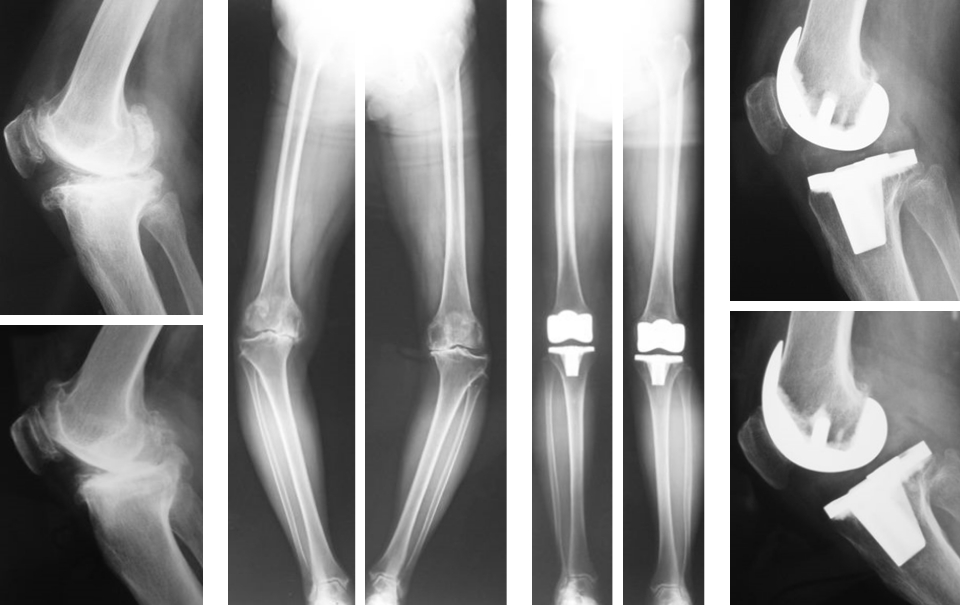

TKAはおもにOA(図2,3)やRA(図4)、UKAは骨壊死(図5)やOAの内側罹患例に行います。左右罹患例には両膝同日手術も施行しています(図3)。手術の目的は除痛、膝関節機能の回復によるADL、QOLの改善です。

人工膝関節は多機種ありますが、当科では自家組織(骨や靭帯)温存に配慮して、主に前十字靭帯のみ切除するCR型を選択し、膝蓋骨は非置換、セメントレス用コンポーネントを用いています(図2)。後療法は両側例でも翌日から離床と荷重を許可し、入院加療は約2週間です。

図3 両側OAに対する両側同日TKA

図4 RAに対するTKA